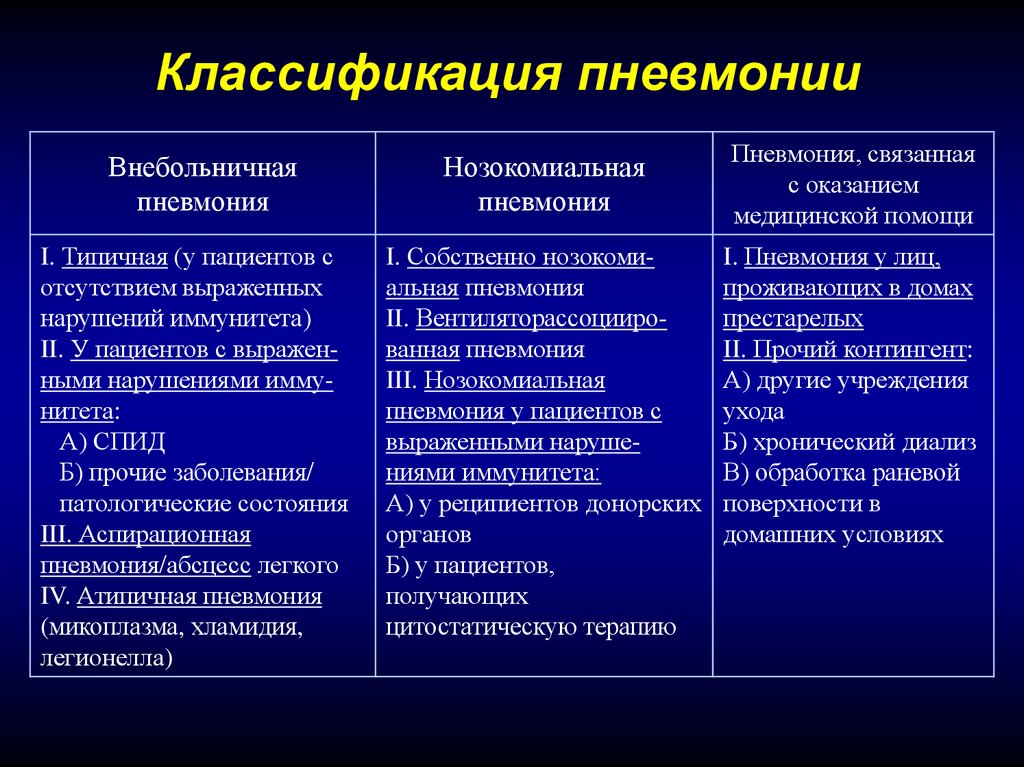

ТАСС-Досье. Пневмония (или воспаление легких) — острое респираторное инфекционное заболевание, вызывающее поражение легочной ткани. Несмотря на то, что заболевание распространено повсеместно, в наибольшей степени, по данным Всемирной организации здравоохранения (ВОЗ), от него страдают дети и семьи в странах Южной Азии и Африки (южнее пустыни Сахара).

Пневмония может протекать в острой, подострой (затяжной) или хронической формах, в тяжелых случаях не исключен смертельный исход. Смешанная вирусно-бактериальная инфекция отягощает течение болезни. В зависимости от вовлеченности легких в воспалительных процесс выделяют одностороннюю (когда поражено одно легкое) и двухстороннюю (оба легких) пневмонию.

Пневмонию могут вызывать различные микроорганизмы: преимущественно бактерии (пневмококки, гемофильная палочка, стафилококки, стрептококки и др.), вирусы (гриппа, респираторно-синцитиальный вирус, риновирусы, аденовирусы и др.), редко грибки и паразиты (аскариды, стронгилоиды и др.).

В последнее время отмечается тенденция к увеличению количества атипичных пневмоний, причиной которых становятся нехарактерные (атипичные) возбудители: например, вирусы и внутриклеточные бактерии легионеллы, микоплазмы, хламидии.

Сергей Авдеев: Нынешняя атипичная пневмония, она же вирусная пневмония, действительно отличается от внебольничной пневмонии, с которой мы имели дело раньше. Хотя вирусные пневмонии известны нам достаточно давно. Вспомните пандемию гриппа h2N1. Но пневмония, связанная с новым коронавирусом, протекает необычно. Это связано с тем, что у пациентов с COVID-19 мы наблюдаем самые разные степени повреждения легких с абсолютно разными клиническими проявлениями. Например, появились пациенты, у которых подтвержден новый коронавирус лабораторными тестами.

Если вы заболели пневмонией, находясь в больнице и не находясь на искусственной вентиляции легких, это называется «внутрибольничной» пневмонией. Но большинство людей заболевают «внебольничной пневмонией», что означает, что они не заразились ею в больнице.